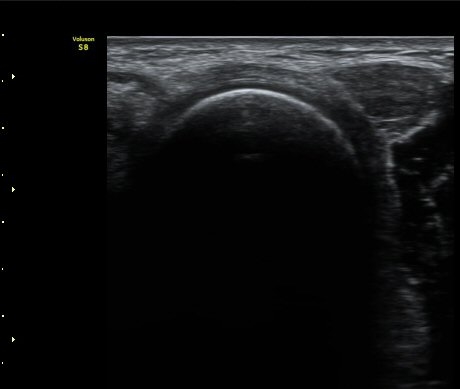

ÆÈ²ÞÄ¡  ¾ÕÂÊ¿¡¼­ ½ÃÇàÇÑ ¿ä°ñµÎ Á¾´Ü¸é°Ë»ç¿¡¼­ ƯÀÌ ¼Ò°ßÀ» º¸ÀÌÁö ¾ÊÀ½(±×¸² 1).

ÆÈ²ÞÄ¡ ¿ÜÃø¿¡¼­ ½ÃÇàÇÑ ¿ä°ñµÎ Á¾´Ü¸é°Ë»ç¿¡¼­ ¿ä°ñµÎ¿Í ¿ä°ñ °æ°èºÎ°¡ ¿¹°¢À¸·Î ÀÌÇàµÇ°í

°æ°èºÎ¿¡ ¼Ò·®ÀÇ ¼ö¾×Àú·ù°¡ °üÂûµÊ(±×¸² 2)